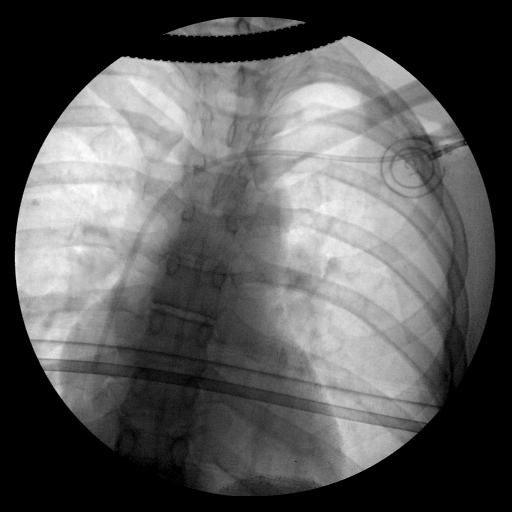

They checked my lungs during inspiration (first image) and expiration (second image): you can clearly see Portia with the catheter getting into my subclavian vein.

Luckly enough, I didn’t have a pneumothorax, so we went ahead with chemotherapy.